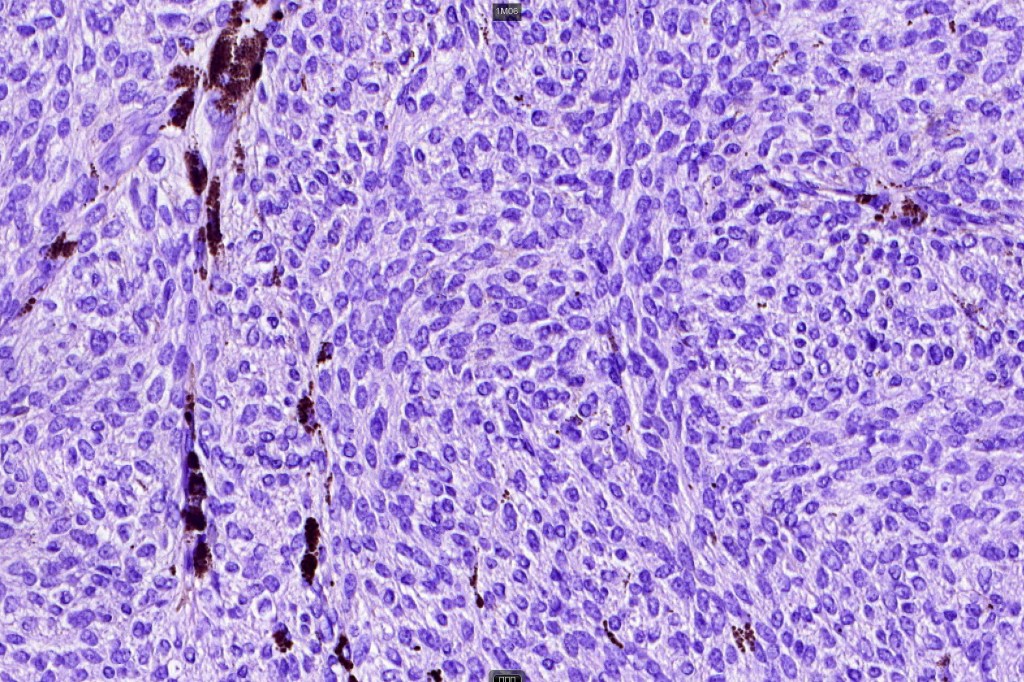

Histologically, it is characterized by a dense population of spindled, dendritic melnanocytes & melanophages with variable fibrosis. It may sometimes represent a component of a combined nevus. Mitotic activity is not usually present and pleomorphism is absent (see atypical blue nevus below). Involvement of the arrector pili muscle is not uncommon.

•Mitoses are typically very sparse or absent

•No atypical mitoses

•No Necrosis or lymphovascular invasion